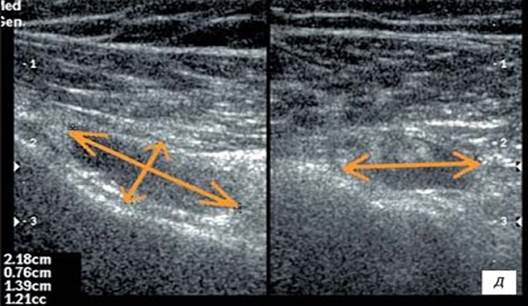

Высокую эффективность терапии препаратами коллагена для внутрисуставного и периартикулярного введения и геля на основе полинуклеотидов подтверждено результатом УЗИ исследованием и МРТ (рис.3, 4,5).

/Scherbakov.files/image003.jpg)

А B

A — до лечения В — после лечения.

Стрелками обозначено количества синовиальной жидкости в полости сустава. Наблюдается уменьшение количества жидкости после проведенной терапии за счет уменьшения воспаления.

Рисунок 3. Изменение количества жидкости в сумке сустава при исследовании в В-режиме, Long Axis

/Scherbakov.files/1.png)

A — до лечения: сухожилие утолщено (до 0,8 см), умеренно неоднородной структуры, сниженной эхогенности; В — после лечения: через 2 мес. после окончания лечения: отмечается уменьшение толщины сухожилия (до 0,6 см), структура прежняя, эхогенность умеренно повышена.

Рисунок 4. Сухожилие надостной мышцы в В-режиме, Long Axis